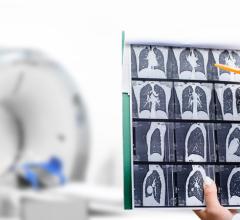

June 18, 2024 — A new study led by American Cancer Society (ACS) researchers shows less than one-in-five eligible ...

June 17, 2024 — MRI has transformed neuroscience research over the past 50 years, but research participants have had to ...

June 17, 2024 — Avenda Health, an AI healthcare company creating the future of personalized prostate cancer care ...